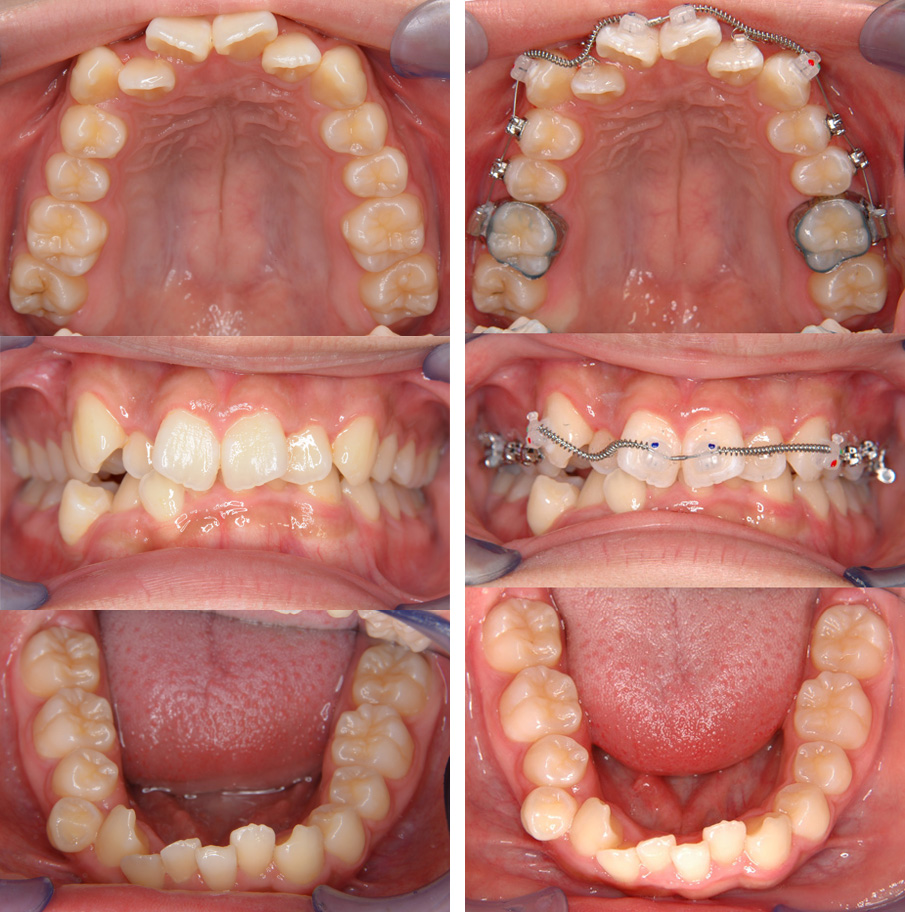

この患者様は歯ならびのガタガタ(叢生)の程度は比較的大きいのですが,上下前歯の重なりが大きく下の歯が見えていません(過蓋咬合).このような場合,歯を抜いてしまうと過蓋咬合の改善が難しいため歯を抜かずに(非抜歯)治療します.

下左:初診時の記録(歯ならびのガタガタに加え,下の前歯がほとんど見えない過蓋咬合という状態です)

下右:上顎にのみ装置を装着,治療開始時

下左:治療開始後5か月で,下顎にも装置を装着

下右:治療終了時(上顎に装置装着後2年5か月)

-治療に関する詳細-(1)主訴(患者が一番気になること):ガタガタ,咬みづらい.(2)診断名:叢生・過蓋咬合(歯並びのガタガタ・前歯の上下方向の重なりが大きい).(3)治療開始時年齢:15歳5か月.(4)使用した装置:マルチブラケット装置.(5)抜歯部位:非抜歯(歯を抜かない治療).(6)治療期間・治療回数:2年5か月(マルチブラケットで歯を動かした期間〈治療回数21回・難易度により回数は増えます〉、その後、保定(歯を安定させる)治療〈治療回数7回〉に移行・「矯正装置について」ページ下段参照).(7)費用の目安:957,000円/税込 (870,000円/税別) 2024年の治療費用・保定治療2年分を含む総額/検査・診断料別途.(8)リスク・副作用など:a.矯正力により痛みが出ることがあります. b.矯正装置によりむし歯のリスクが高まります.c.装置の脱離などにより臨時の受診が必要となることがあります.d.治療により歯の根が短くなることがあります.e.まれに歯と骨が癒着し動かないことがあります.f.治療後歯並びは生涯変化します.g.舌の癖・顎骨の成長・治療前の難易度などにより理想的咬み合わせと異なる仕上がりとなることがあります.h.「転医」により治療に時間を要したり治療方針が変更となことがあります.さらに詳しい情報は「矯正治療のリスク・副作用」ページを参照ください.